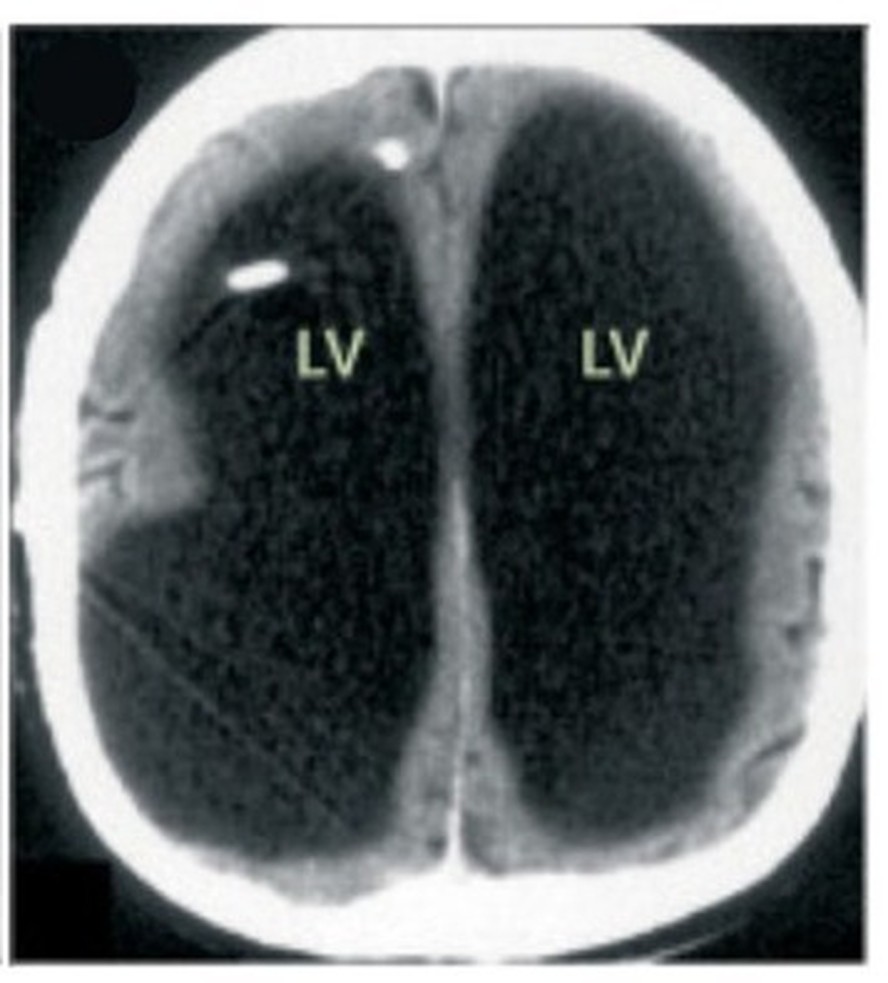

Depois que os médicos realizaram tomografias e ressonâncias, pois acreditavam que o paciente pudesse ter uma condição neurológica que estava afetando suas terminações nervosas, descobriram que, diferente do que pensavam, ele na verdade tinha uma enorme bolsa de líquido onde seu cérebro deveria estar.

Nas imagens de seu cérebro, compartilhadas com o periódico médico The Lancet, a parte principal de sua área cerebral aparece preta, que é onde havia acúmulo de fluido. Isso fez com que seu cérebro se espremesse em uma camada estreita, que pressionava a borda do crânio.

Ele então foi diagnosticado com um caso grave de hidrocefalia. Os médicos então voltaram para ver o histórico médico do paciente. Aos seis meses de idade, ele passou por uma derivação ventrículo-atrial devido a uma causa desconhecida.

Aos 14 anos, ele desenvolveu ataxia (baixo controle muscular) e paresia (perda parcial da força muscular) na perna esquerda. A derivação foi ajustada, o que resolveu completamente seus sintomas. Entretanto, os sinais ressurgiram na idade adulta e os médicos determinaram que ele tinha um tipo de hidrocefalia causada por um bloqueio em uma das vias de drenagem do cérebro.

Apesar do caso ter sido relatado em 2007, ele voltou recente nas redes sociais. Lionel Feuillet, neurologista da Universidade Mediterrânea de Marselha, disse na época em que o relato do caso foi publicado que a equipe médica ficou “muito surpresa quando o paciente foi examinado pela primeira vez na tomografia computadorizada. O cérebro era muito menor que o normal. Este caso é único em nosso conhecimento”, diz.